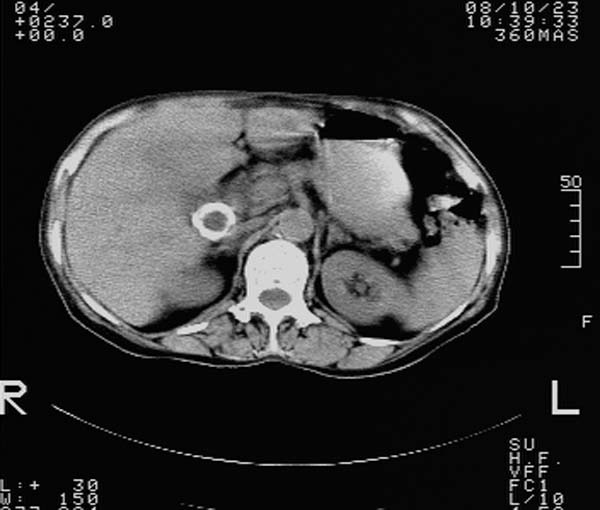

f,67y。反复右上腹痛。余无异常。

前五幅未服造影剂。后面图像有上传重复的。请战友们发表意见。

胆囊结石、胆囊癌伴邻近脏器受侵,不除外黄色肉芽肿性胆囊炎,建议增强扫描。肝多发囊性占位性病变,囊肿或囊性转移。

胆囊结石、胆囊癌伴邻近脏器受侵,肝转移可能

胆囊内结石,胆囊壁不规则增厚,胆囊胃窦区解剖结构欠清晰,楼主提示为少见病,考虑bouveret综合征?黄色肉芽肿性胆囊炎?肝内多发低密度占位,建议增强或b超

bouveret综合征(胆石性十二指肠幽门梗阻)应重点考虑。期待结果!

考虑bouveret综合征?黄色肉芽肿性胆囊炎?肝内多发低密度占位,囊肿?建议增强!